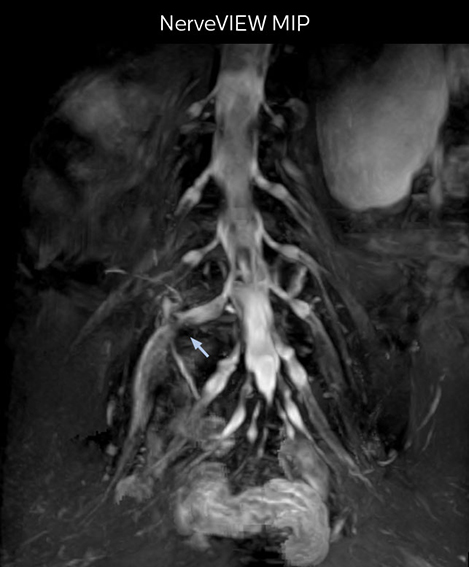

“In patients with lower extremity neurological symptoms, NerveVIEW helps us to determine the disease matching the patient’s symptoms by directly visualizing the nerves. We use the sequence mainly, when there is suspicion of intraforaminal stenosis, extraforaminal stenosis or lateral disc herniation, which is often based on routine T2- and T1-weighted images. Additionally, the excellent depiction of the course of nerves makes NerveVIEW a good navigator when applying treatment such as block therapy or surgery.”

Northern Fukushima Medical Center (NFMC) Imaging Center uses the 3D NerveVIEW sequence for performing MR neurography, particularly in patients with pain and weakness in the lower limb. “It is included in about 20% of the approximately 150 lumbar spine MRI exams each month at NFMC, and can help us to determine if structures are impinging on the nerves,” says Hajime Tanji, RT, MRI technologist at NFMC.

“In such case, we would then browse through axial T2-weighted MR images slice by slice and mentally reconstruct the actual situation based on both radiculography and MRI. Fortunately, NerveVIEW can now very well show nerve courses and presence of nerve compression or edema in one single image series.” “We have often seen NerveVIEW directly depict details of the nerve compression that were not observed by radiculography. Therefore, we think that with NerveVIEW we can reduce the number of invasive examinations, especially for some patients with lumbar plexus symptoms.”

“The intra-luminal signal of veins, especially around the intervertebral space, can be suppressed well with NerveVIEW. As a result, we can easily observe the detailed nerve structure around the posterior ganglion,” he says. “This is why we use 3D NerveVIEW for intraforaminal stenosis and extraforaminal stenosis/herniation (lateral disc herniation). On the other hand, if herniation is suspected to exist inside the dorsal root ganglion (DRG), balanced TFE or ProSet-FFE is applied. NerveVIEW is not suitable for evaluating the median type of herniation.” The SE-EPI DWI-based method for MR neurography works well for large FOV exams like whole-body MRI, but focal examination of nerves is often limited by the attainable spatial resolution (both inplane and slice direction) and geometric distortion. “3D NerveVIEW achieves higher in-plane resolution – close to our other routine spine sequences – and the source images can be used instead of adding a fat-suppressed T2-weighted sequence,” Tanji says.

According to Tanji, methods such as ProSet FFE, STIR or 3D VISTA are anatomically nonselective because background signals, for instance from blood vessels, often interfere with nerves, which hampers evaluation of details, especially at the peripheral side of the nerves.

“NerveVIEW can clearly show nerve courses and presence of nerve compression. However, when multiple abnormalities are seen, it can still be hard to determine which nerve is causing the symptoms,” says Dr. Yabuki. “In our experience so far, we see abnormal findings on NerveVIEW in about 70% of elderly patients. As the pain is usually caused by only one nerve, we thus need to find the exact corresponding nerve.” “With a nerve root block, the patient's pain is improved by infiltration of local anesthesia directly around the nerve root considered to be responsible. Knowing such nerve root block findings prior to image interpretation, helps to easily recognize abnormal findings on NerveVIEW as well. In other words, without a priori knowledge, based on symptoms and/or nerve root block findings, we must be aware of the possibility of overdiagnosis.”